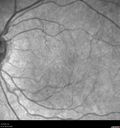

Perifoveal Microaneurysm - Not Diabetic (also reticular pseudodrusen)353 views87 year old female with fluctuating macular edema in the right eye from a perifoveal MA. (no treatment). VA 20/40 OU00000